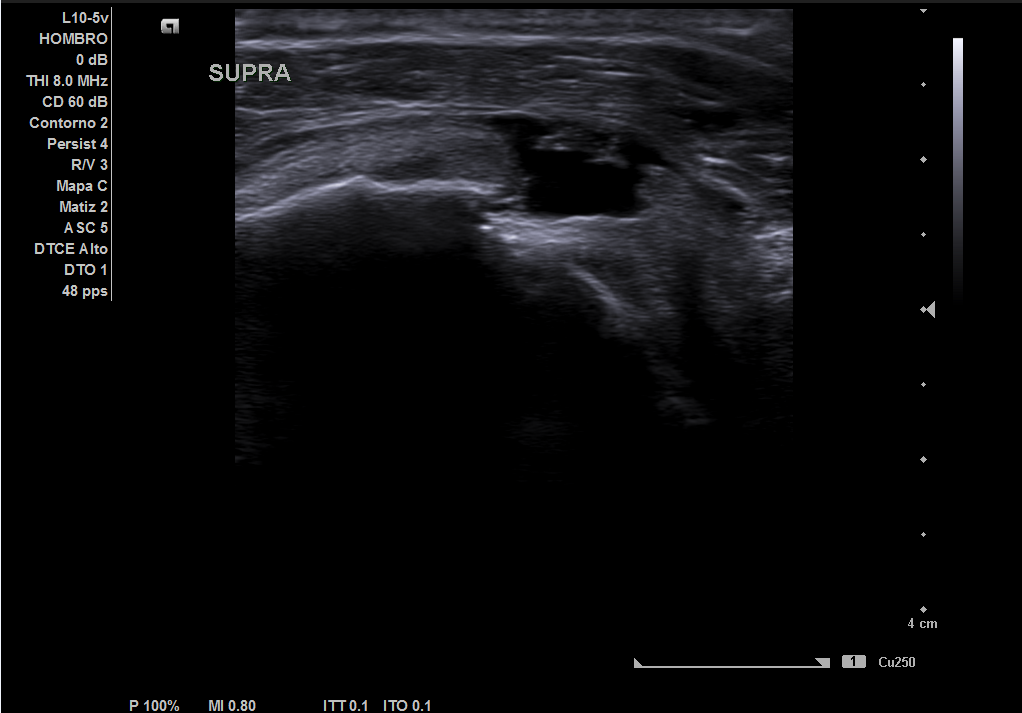

En la ecografía realizada observamos una rotura completa del tendón supraespino, rotura parcial del subescapular y severo derrame peritendón del bíceps junto con derrame articular glenohumeral.

Resonancia magnética: rotura completa del supraespinoso, rotura completa del subescapular, rotura miotendinosa del infraespinoso, severo derrame articular glenohumeral.

Juicio diagnóstico: rotura manguito de los rotadores (rotura completa supraespinoso).